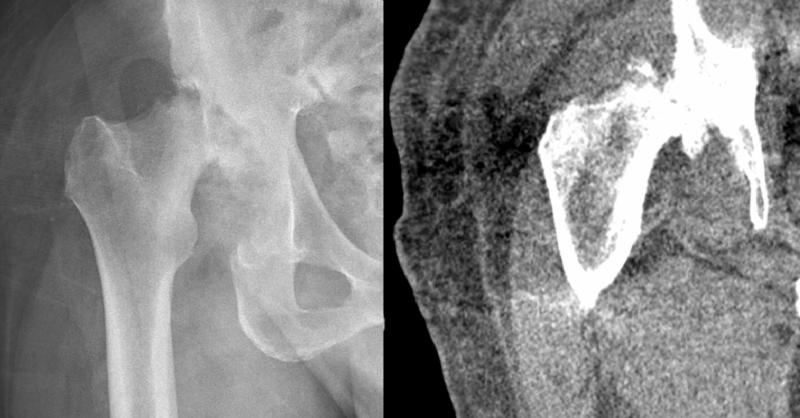

Septic arthritis is inflammation of the joints secondary to an infectious etiology such as bacterial, fungal, mycobacterial, viral, or other pathogens. It is usually monoarticular, however, polyarticular septic arthritis involving many or smaller joints may also occur. Septic arthritis is joint inflammation secondary to an infectious etiology, usua